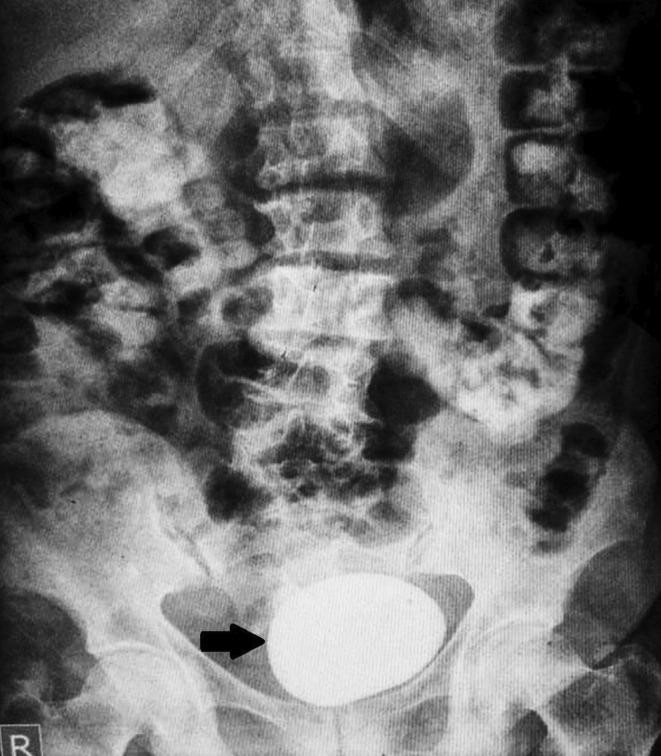

Vesicovaginal fistula associated with massive bladder calculi: An urogynecological case report.

In developing countries, VVF mainly occurs due to obstructed labor unlike developed countries where common causes are radiotherapy and malignancy. Due to social taboos, patients do not seek medical attention for problems like urinary incontinence and dysuria, thus presenting very late.